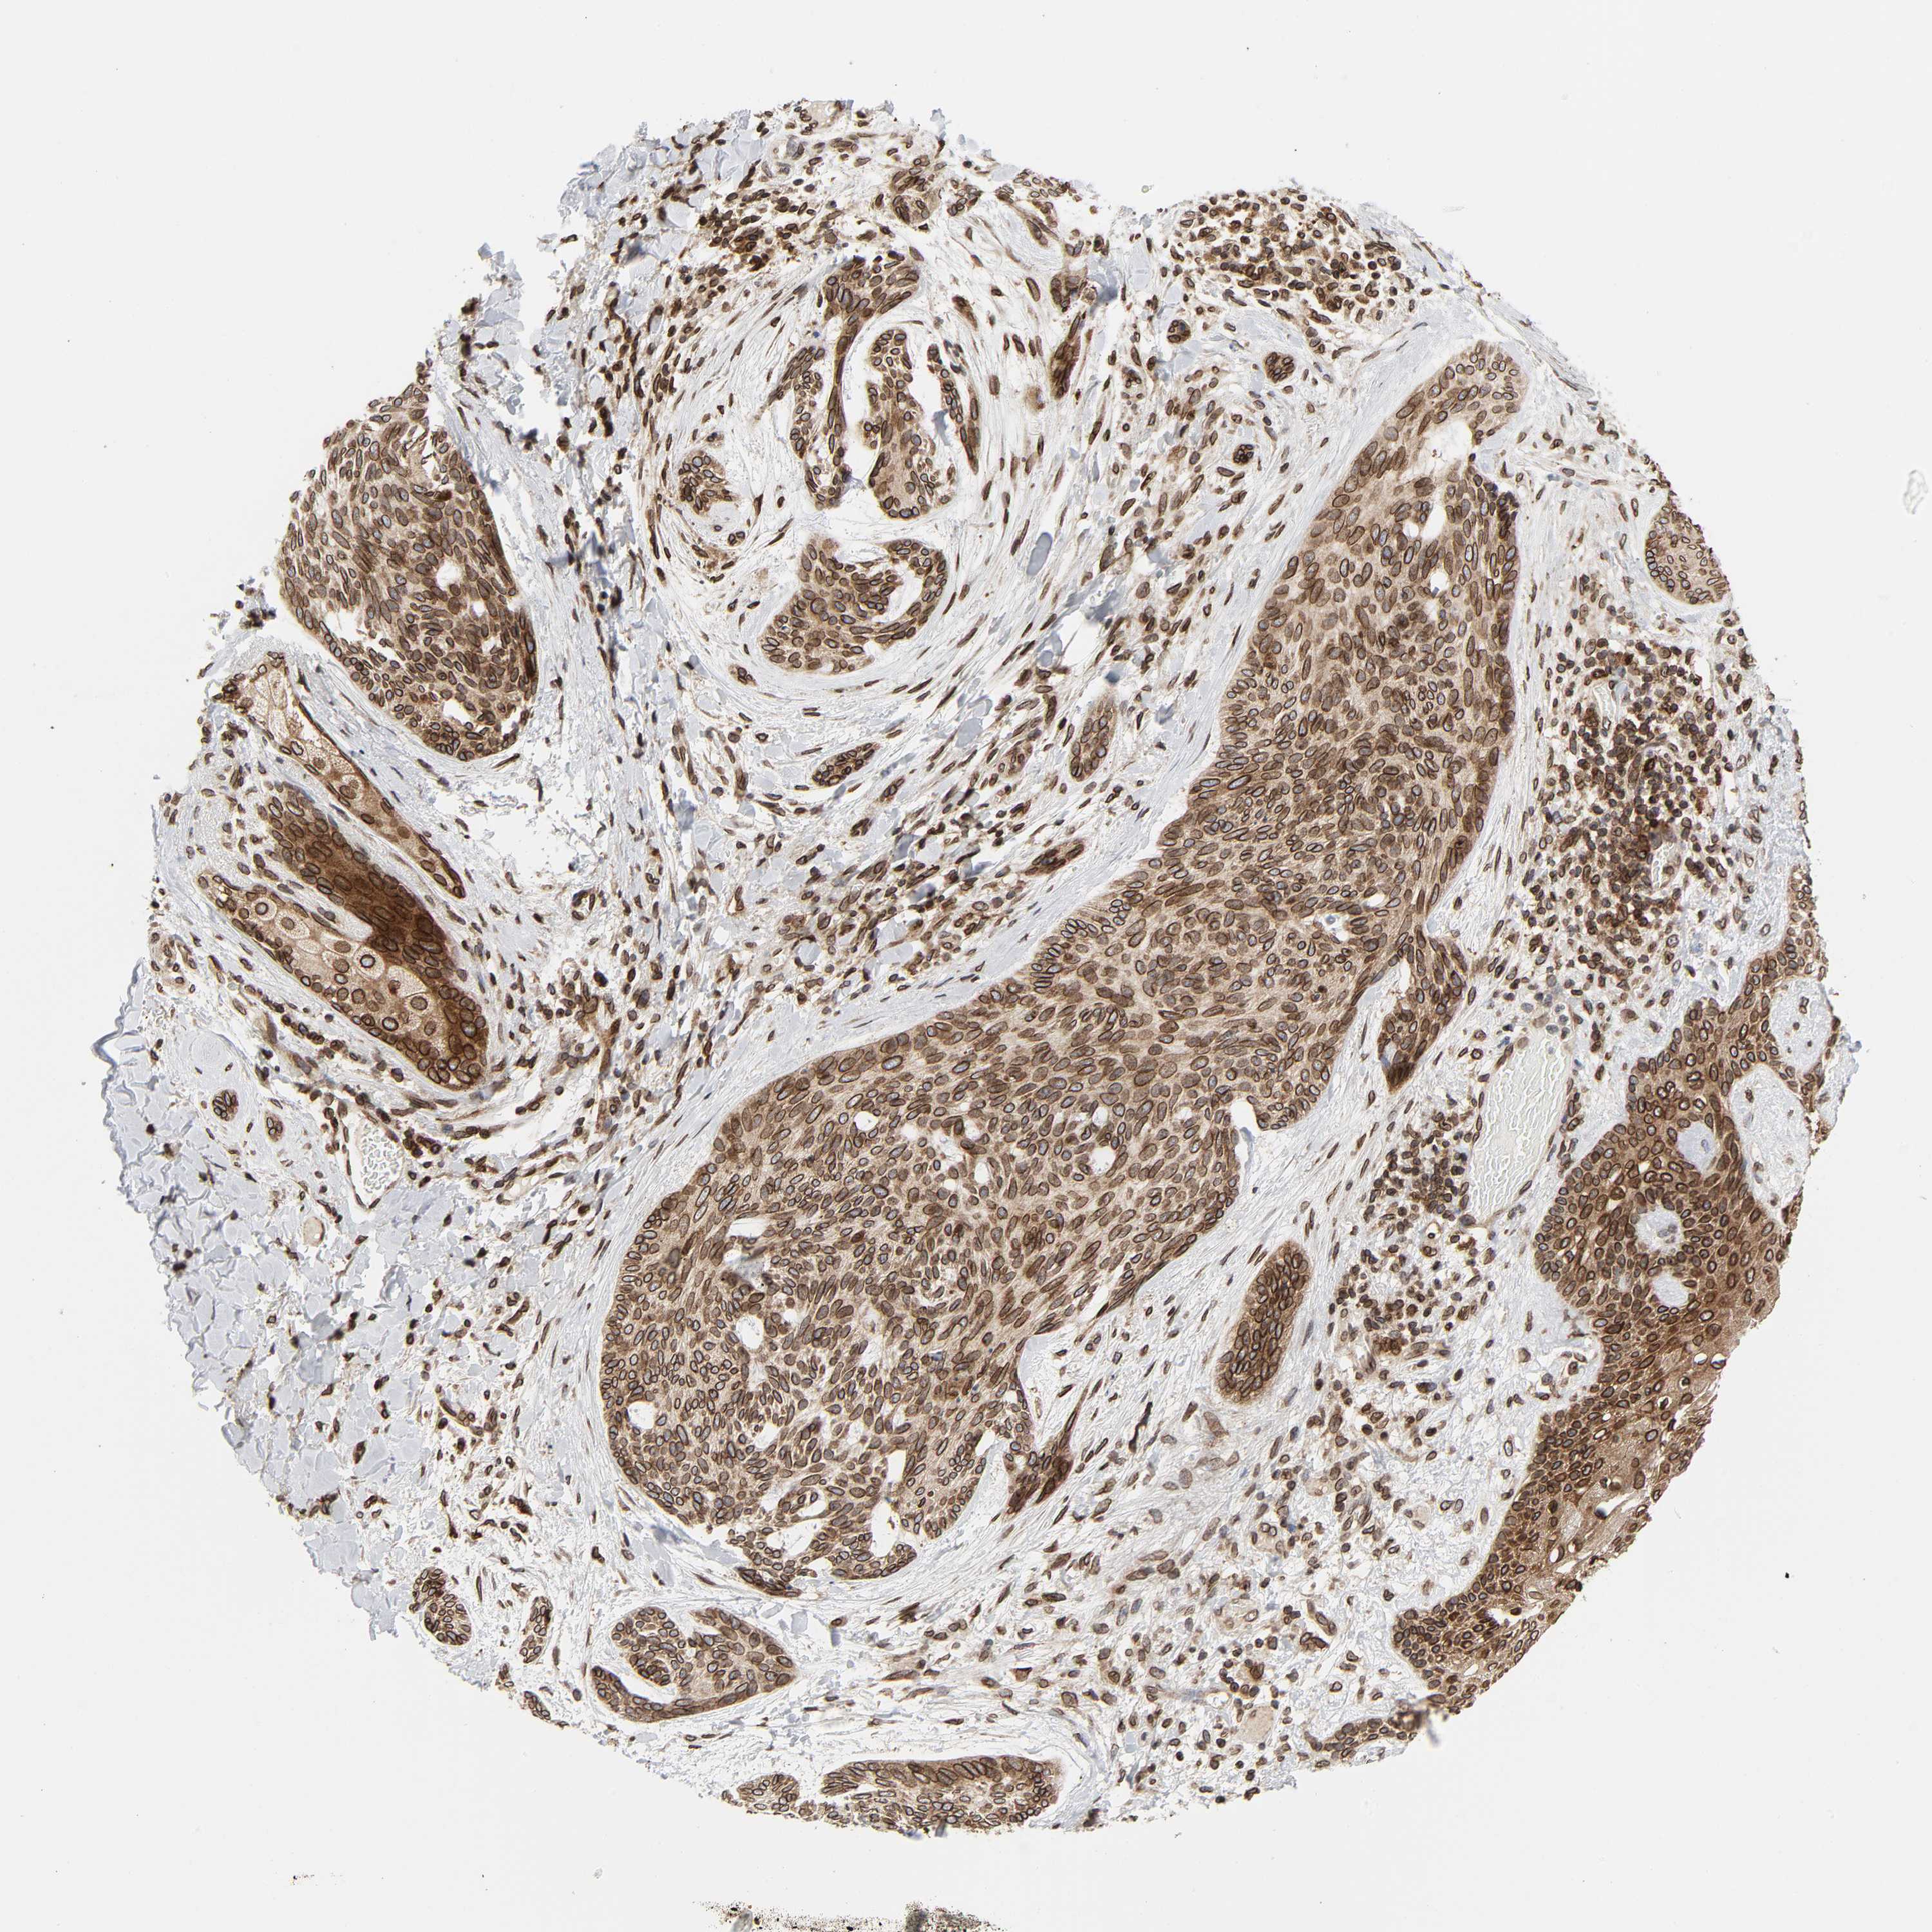

SKIN CANCER - Protein expressioni

A mouse-over function shows sample information and annotation data. Click on an image to view it in a full screen mode. Samples can be filtered based on level of antibody staining by selecting one or several of the following categories: high, medium, low and not detected. The assay and annotation is described here.

Each image is clickable and will lead to virtual microscopy that enables deeper exploration of all samples and also displays staining intensity scores, fraction scores and subcellular localization as well as patient and tissue information for each sample.

Antibody HPA050110

Antibody CAB004293

Staining

High

Intensity

Strong

Quantity

>75%

Location

Nuclear

Basal cell carcinoma

Squamous cell carcinoma, NOS

Squamous cell carcinoma, metastatic, NOS